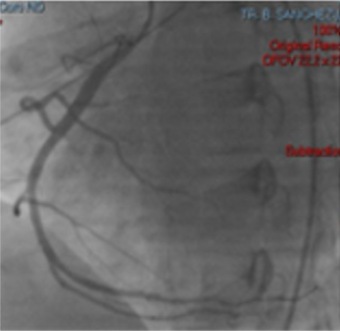

Electrocardiogram with right leads shows ST segment elevation in V4 (Figures 2 & 3). ACTP is performed by total occlusion in the distal third of the right coronary artery, without atherosclerotic lesions, other normal-looking coronary vessels without atherosclerotic lesions. Upon admission to the coronary intensive care unit, he is found with the following physical examination: Hemodynamic with blood pressure 80 / 40mm Hg, with norepinephrine at 0.05gammas and dobutamine at 5 gammas. Cardiovascular, neck with jugular engorgement grade II, no carotid murmurs, with apical impulse in sixth left intercostal space, anterior axillary line, high parasternal lift, Chavez integrates suggestive of pulmonary hypertension, paradoxical splitting of second pulmonary noise. Puff with pulmonary epicenter, mesosystolic, rough, intensity IV / VI, long duration, rough-blowing quality. Mesothelediastolic Erb point (accessory aortic), grade III / VI, blowing quality. Puff with tricuspid epicenter, holosystolic, intensity III / VI, regurgitant, blowing quality. I blow with mitral epicenter, holosystolic, grade II / VI, regurgitant, blowing quality, short duration. Respiratory without rales, crackling. Globose abdomen at the expense of adipose panicle, with no evidence of peritoneal irritation. Lower extremities with edema +++ / +++, filiform pulse in 4 strictures.